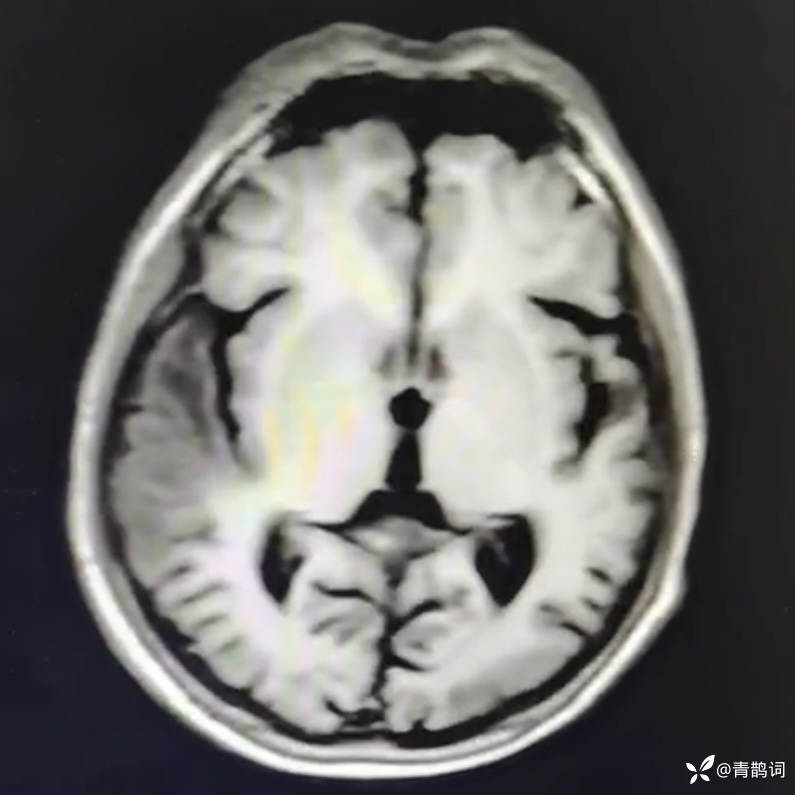

乐痴于医等 2人推荐简要病史:42岁男性,记忆力下降及听力下降一年余。既往体健,否认前驱感染病史。否认家族史。三个月前就诊于当地医院,自述腰穿脑脊液乳酸增高。现就诊于我院,查体记忆力下降,计算力下降,定时定向差,吟诗样语言。完善磁共振如下:

T1: